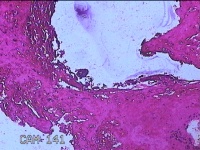

子宫腔内容物

性别

女

年龄

33岁

临床诊断

异常子宫出血;药流不全?宫腔占位

一般病史

阴道流血9天。

标本名称

大体所见

灰白暗红色不规则碎组织1.5x1x0.3cm一堆,未发现明显的绒毛样组织。

不具诊断价值。